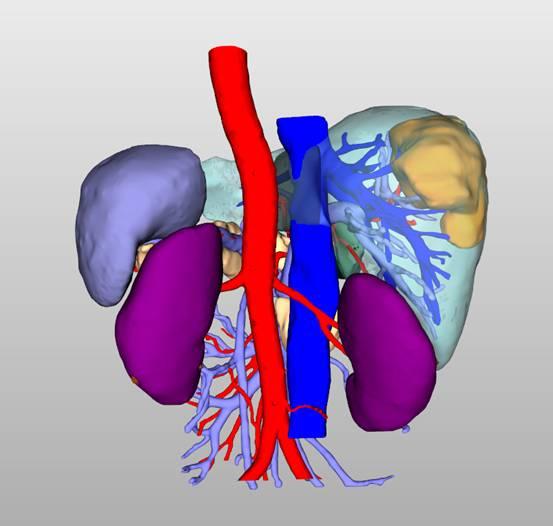

图 7:肝脏 3D 可视化

图 8:肝脏 3D 可视化

图 9:肝脏 3D 可视化